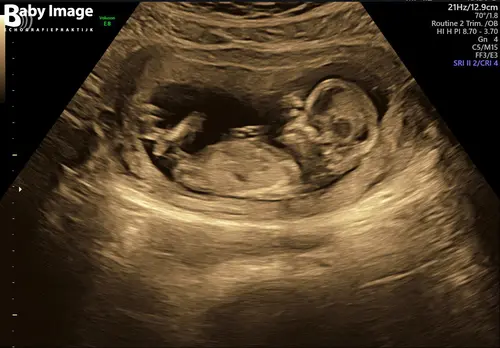

Vandaag de 13 weken echo gehad (13wk 2 dagen). Zien jullie op deze foto een Nub? Een jongetje of meisje?💙💖

Foto 2